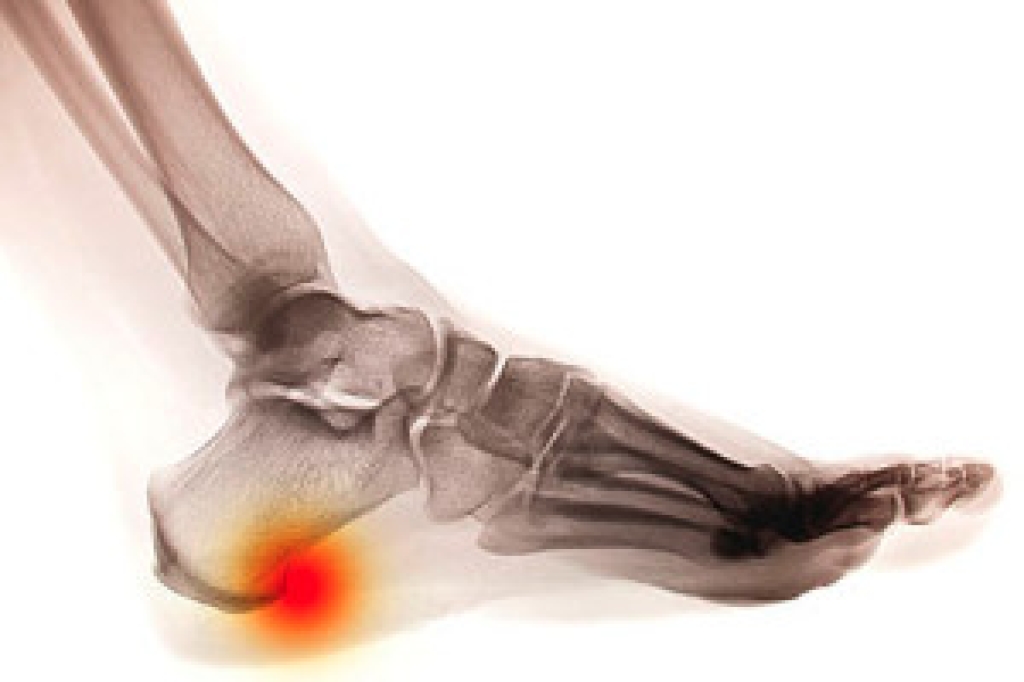

How Do Heel Spurs Develop?

A heel spur is a regeneration of a bone that forms on the sole of the foot. Additionally, the development of this ailment can appear in the area where the Achilles tendon connects to the heel and may produce severe pain. In most cases, a heel spur will gradually develop, and is often caused by strain experienced by the muscles and ligaments. Causes of this type of discomfort may originate from shoes that fit incorrectly, additional body weight the feet must endure, or an injury that caused the heel to bruise. Paying close attention to the general health of the feet may be a successful prevention technique for heel spurs. This may include noticing any type of aches and pain that may appear, especially on the sole of the foot. Moderate relief may be obtained from resting the foot in addition to performing gentle stretching exercises. It’s suggested to consult with a podiatrist for treatment options for heel spurs, which may include surgery.

Heel spurs are formed by calcium deposits on the back of the foot where the heel is. This can also be caused by small fragments of bone breaking off one section of the foot, attaching onto the back of the foot. Heel spurs can also be bone growth on the back of the foot and may grow in the direction of the arch of the foot.

The pain associated with spurs is often because of weight placed on the feet. When someone is walking, their entire weight is concentrated on the feet. Bone spurs then have the tendency to affect other bones and tissues around the foot. As the pain continues, the feet will become tender and sensitive over time.